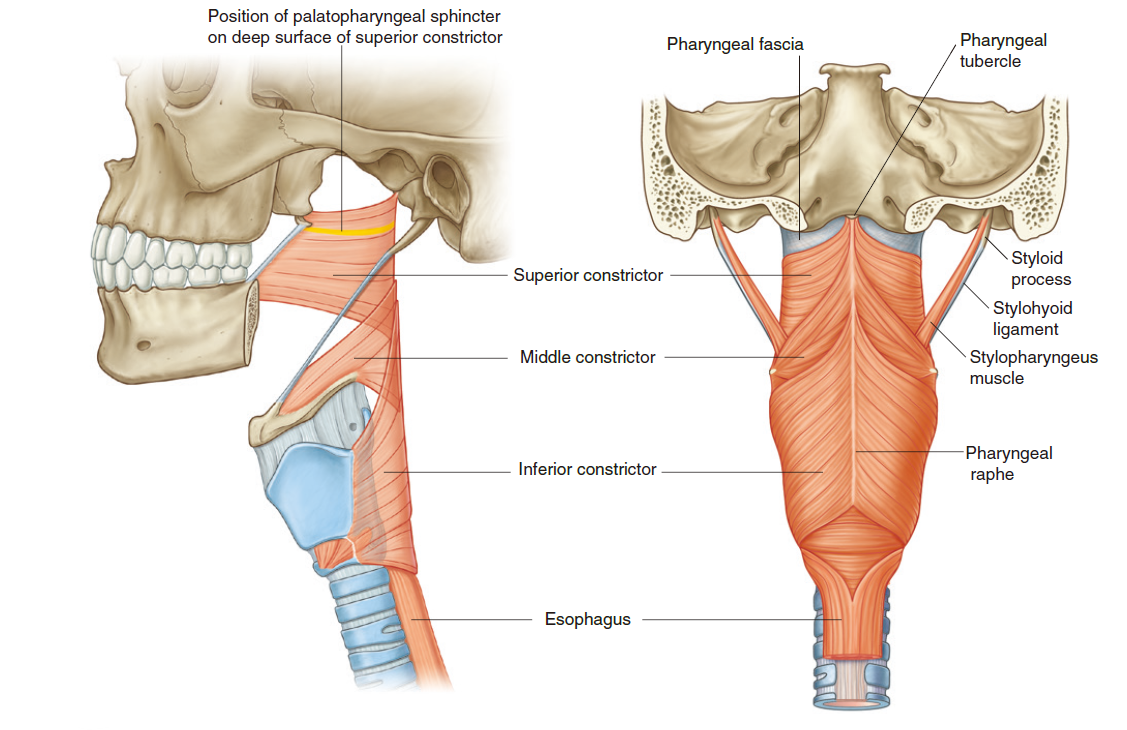

Muscle

外部

-

pharyngeal constrictor

- CN X (Pharyngeal plexus) 控制

- 環狀肌肉

外 內 Sup Pterygomandibular raphe pharyngeal raphe Mid Hyoid bone 的 greater horn,

Sup. pharyngeal constrictorInf Thyroid cartilage 的 oblique line,

Cricoid cartilage -

Stylopharyngeus

- 穿入Sup. Mid. pharyngeal constrictor之間

- CN IX 支配